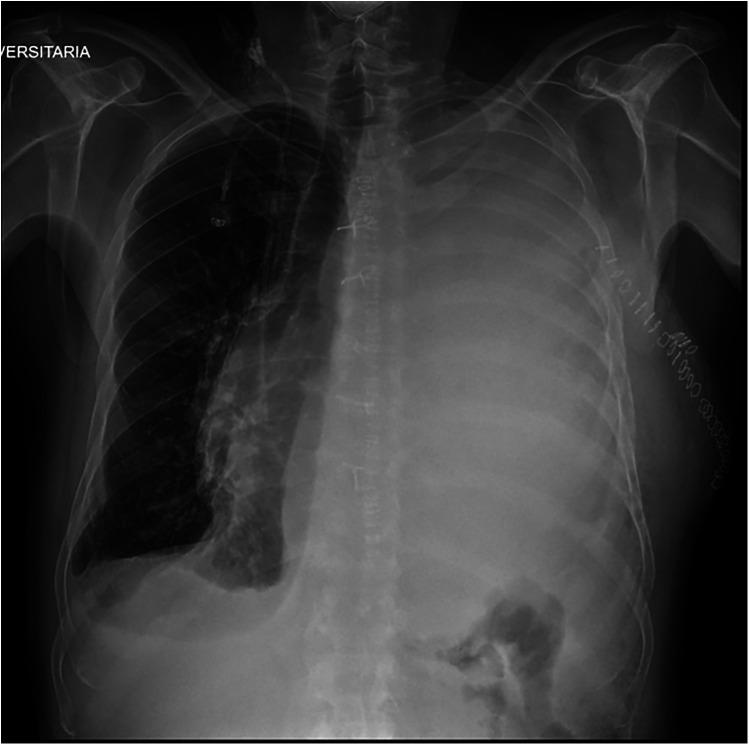

We present the case of a 62-year-old man diagnosed with SMARCB1-deficient mediastinal sarcoma who underwent left pneumonectomy and subsequently developed a left-sided chylothorax on postoperative day 16. Initial management with conservative strategy first, including two lymphography procedures with attempted embolization, was unsuccessful. Consequently, we proceeded with thoracic duct ligation via right-sided VATS, employing indocyanine green (ICG) fluorescence to aid in the identification of the thoracic duct. Given the prior left pneumonectomy, a single-lumen endotracheal tube with a bronchial blocker was used to selectively exclude the right lower lobe during the procedure.

This case highlights the use of ICG fluorescence in facilitating the identification and ligation of the thoracic duct in a patient with left-sided chylothorax following left pneumonectomy.